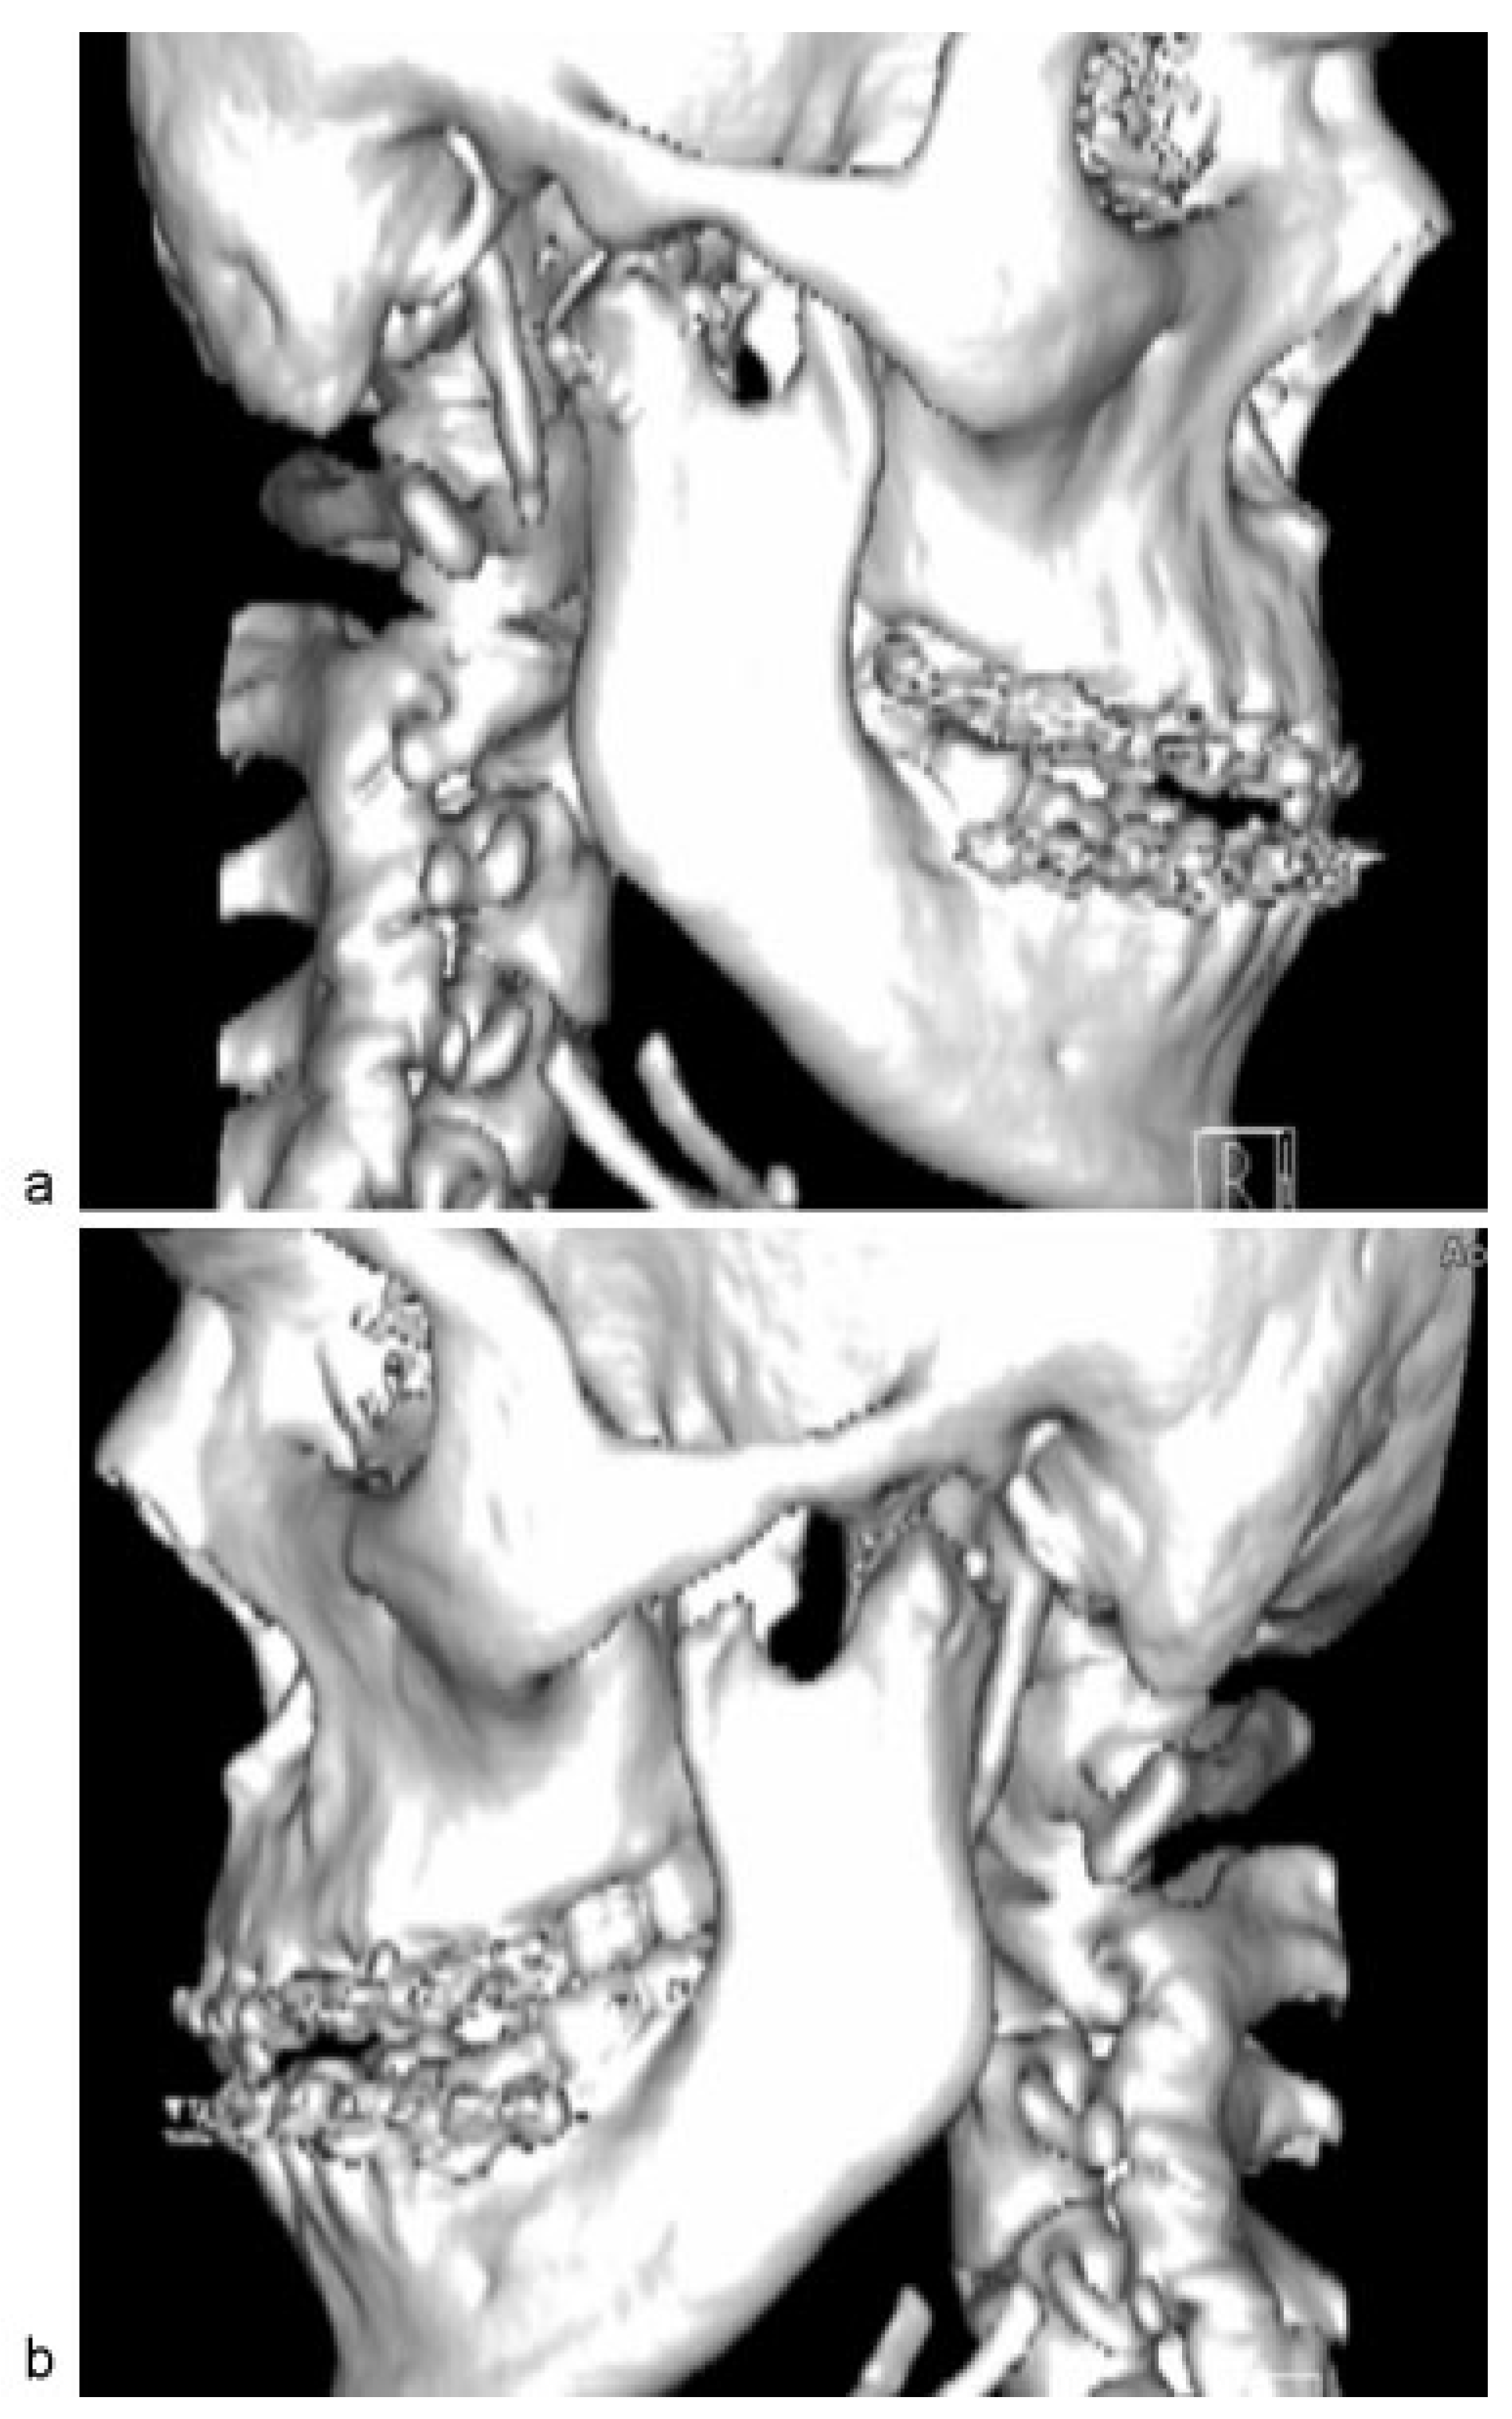

The glenoid fossae, articular eminences, and both dislocated mandibular condyles were fully exposed. Wasting of the temporalis muscle was noted. It became clear at this point that initial manipulation of the mandible to relocate the condylar heads into glenoid fossae was unsuccessful due to the presence of thick fibrous tissues around the TMJ capsules ([Figure 3]). These fibrous tissues were then released and both TMJ capsules were cut. Rowe’s elevator was used to torque the mandibular condyles back into glenoid fossae. However, difficulty was encountered on the left side; thus, left eminectomy was decided ([Figure 4]).

Figure 3. Unsuccessful repositioning of condyle into glenoid fossae. Right condyle was seen just below the right articular eminence after manual reduction (arrow).